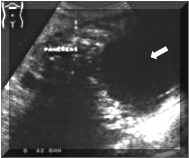

PANCREATIC

PSEUDOCYSTS

Sonographical

Findings:

Sonographically,

are

well

defined

and

have

variable

internal

echogenicity.

hyperechogenicity

suggests

hemorrhage.

may

be

septated

or

contain

debris.

A

pseudocyst

confidently

diagnosed

when

persistent

fluid

collection

is

detected

in

the

clinical

setting

of

pancreatitis.

There

often

mass

effect

on

adjacent

bowel

loops

solid

viscera,

occasionally

definable

fibrous

pseudocapsule

(Pictures

1

2).

Pictures

2.